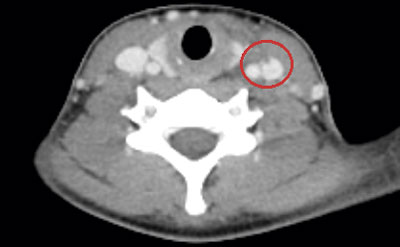

Initialt var diagnosen oklar, men på grund av misstanke om nekrotiserande fasciit i halsområdet gavs trippelbehandling med meropenem, klindamycin, och metronidazol. Tanken på Lemierres syndrom väcktes då datortomografi (DT) av hals och torax visade begynnande trombotisering av vena jugularis interna på vänster sida och embolisering till lungorna (Figur 1 och 2). Diagnosen bekräftades då blododlingar visade växt av Fusobacterium necrophorum i två av fyra flaskor. I svalget växte streptokocker grupp C eller G (slutlig speciesbestämning saknades). Anaerob odling utfördes inte då specifik frågeställning om F necro­phorum inte angavs. Serologin av Epstein–Barr-virus (EBV) visade på genomgången primärinfektion. Dalteparin gavs initialt men sattes ut då senare DT-undersökning inte visade progress av trombosen i jugularis­venen, men däremot tillkomst av pleuravätska (Figur 3). Flickan vårdades på barnavdelning från dygn sex. Där gavs behandling med bensylpenicillin och metronidazol intravenöst. Hon skrevs ut till hemmet med peroral klindamycinbehandling. DT-kontroll (hals, torax) i samband med återbesök en månad senare visade normala förhållanden, varför klindamycin avslutades. Hon mår nu bra.

Figur 1. A: axiala snitt från DT-hals med kontrastmedelsinjektion visar en liten väggfast septisk trombos (inringad) anteriort i vänster vena jugularis interna.

Figur 1. B: sned, sagittalt rekonstruerad DT-bild visar väggfast septisk trombos (inringad) och förstorade cervikala lymfkörtlar.